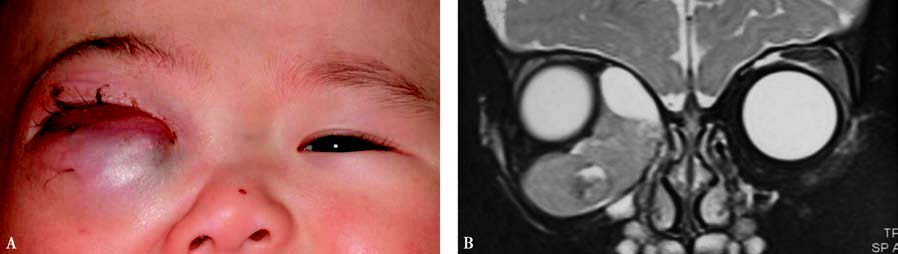

Figure 1 External and imaging features of right orbital rhabdomyosarcoma

A. Proptosis with conjunctival congestion and edema.

B. Coronal T2-weighted MRI showing a hyperintense signal with localized cystic changes.